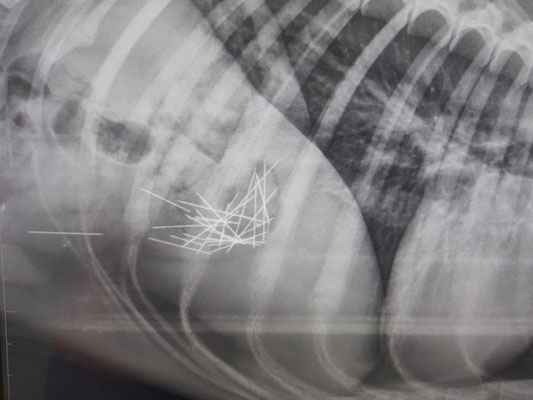

In der städtischen Katzenkolonie wurde ein schwer verletzter Kater aufgefunden. Er rang sichtbar nach Luft, weshalb er umgehend als Notfall zum Tierarzt gebracht wurde. Die Röntgenuntersuchung

offenbarte eine erschütternde Diagnose: Eine Kugel hatte seine Lunge durchschlagen und schwer beschädigt.

Die Verletzung war bereits stark vereitert – eine medizinische Rettung war nicht mehr möglich.

Der Tierarzt konnte den Kater nur noch von seinem Leid erlösen. Die Kosten für die Notfallbehandlung betrugen ca. 100 €.